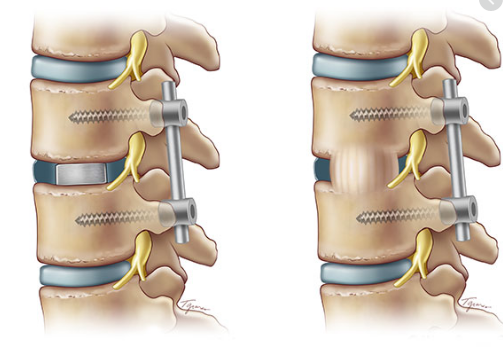

Hình ảnh: Hình ảnh 3D phẫu thuật TLIF

Cho tới nay, phương pháp phẫu thuật nắn chỉnh trượt, cố định cột sống bằng nẹp vít qua cuống, ghép xương liên thân đốt lối sau (sử dung Cage) được cho là hiệu quả nhất, áp dụng phổ biến nhất để điều trị trượt đốt sống thắt lưng.